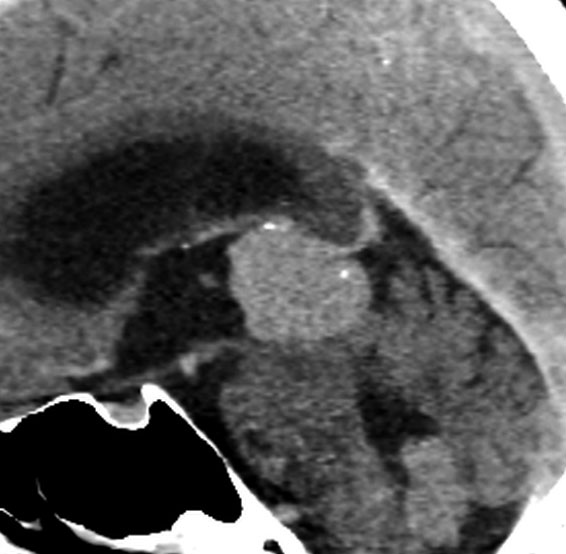

第3脳室開窓後のCTです。左のCTでは小さな石灰化がみられます。右の造影CTでは小さなのう胞部分をのぞいて均一な増強効果がみられます。

MRIガドリニウム増強像です。腫瘍境界がわりにはっきりしていて,中脳や視床に浸潤像がありませんから,松果体芽腫ではないことが解ります。でも,この画像だけからは,松果体細胞腫やジャーミノーマとの区別はつきません。